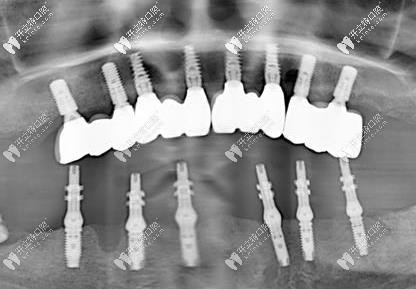

這次種牙僅僅植入了六顆植體,好像是什么ALL-on-6技術(shù),只需要六顆種植體,然后做成一個(gè)連橋冠還是什么就可以了。還真別說(shuō),這個(gè)技術(shù)真厲害啊,六顆植體價(jià)格也沒(méi)有之前的做著貴,價(jià)格方面我也是比較能接受的。

這是種完牙后的照片

讓我稱(chēng)贊的是這個(gè)當(dāng)天種完牙后,效果也是比較不錯(cuò)的,雖然醫(yī)生說(shuō)可以吃一些較軟的食物,但是我還是擔(dān)心,就沒(méi)吃,第二天才開(kāi)始吃的東西,也沒(méi)啥太多不舒服的感覺(jué)。

不知道大家看了我做的半口種植牙效果圖咋樣,我個(gè)人還是非常認(rèn)可這個(gè)技術(shù)的,畢竟不用等那么久,中間的艱辛也不用等啦!